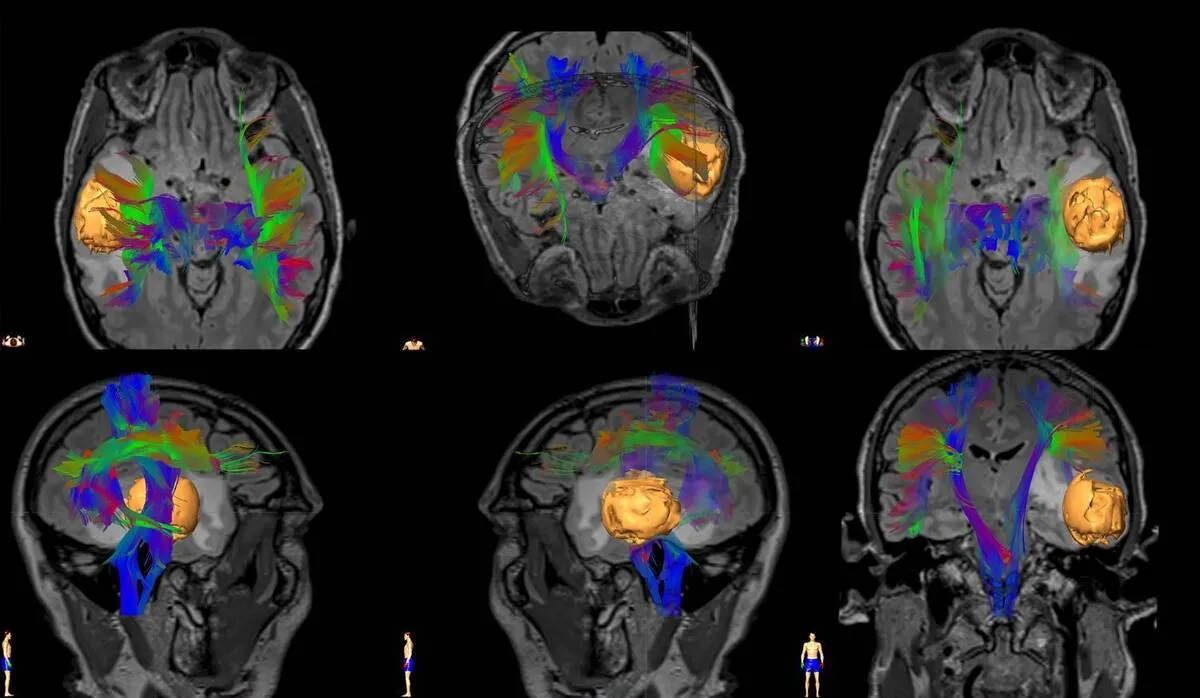

TEHRAN (ANA)- Iranian researchers at Amirkabir University of Technology succeeded in developing a software package to determine the optimal treatment plan (including the dose and timing of chemotherapy and radiation therapy) based on the specific conditions of each patient.

“The aim of this research is to provide a software package for designing a treatment plan (including dosage and timing of chemotherapy and radiation therapy), specifically for patients with glioblastoma, which helps doctors and specialists as a decision aid in finding the optimal treatment,” said Amir Ebrahimizadeh, one of the researchers of the project at Amirkabir University of Technology.

He added that the standard treatment of glioblastoma is a combination of radiotherapy and temozolomide, noting that since separate planning of each of them leads to ignoring the effects of the other method and obtaining unreliable results, the present research is unique in its kind.